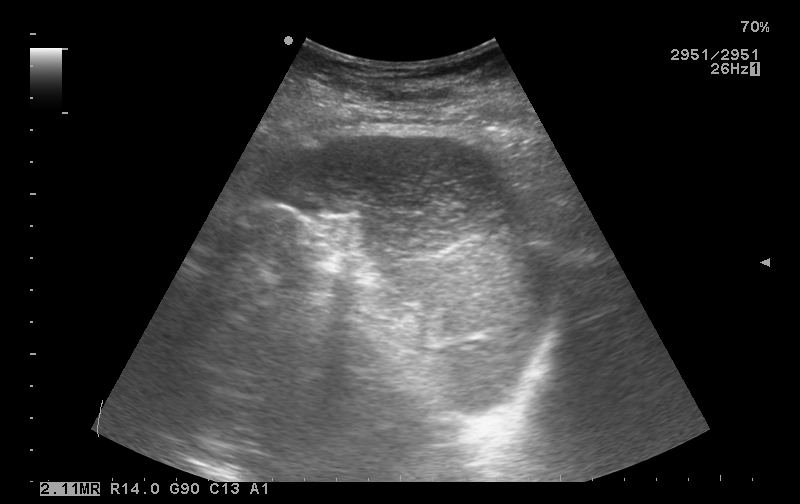

Свежее исследование

20171024_090513_10.jpg

Какие будут мнения?